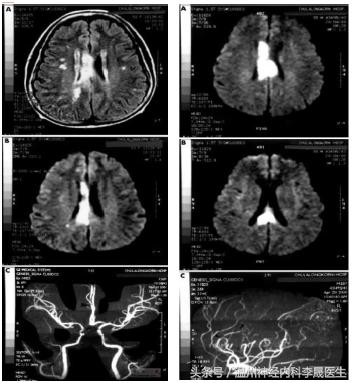

附上一组经典的CT片跟MRI片

先看个病例,女,46岁,主诉;反应迟钝、走路不稳半月。既往史;“高血压”病病史3年,不规律服药,血压控制不详

查体:神经系统:左上肢及右侧肢体肌力5级,左下肢肌力4级,左上肢指鼻试验欠准,与右上肢完成同一动作时笨拙,有时不自主阻挡右手动作,双侧肢体感觉正常,行走似稍宽基底。病理反射未引出。NIHSS评分3分